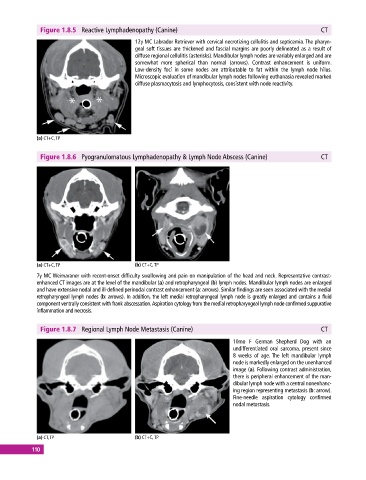

Figure 1.8.5 Reactive Lymphadenopathy (Canine) CT

12y MC Labrador Retriever with cervical necrotizing cellulitis and septicemia. The pharyn-

geal soft tissues are thickened and fascial margins are poorly delineated as a result of

diffuse regional cellulitis (asterisks). Mandibular lymph nodes are variably enlarged and are

somewhat more spherical than normal (arrows). Contrast enhancement is uniform.

Low‐density foci in some nodes are attributable to fat within the lymph node hilus.

Microscopic evaluation of mandibular lymph nodes following euthanasia revealed marked

diffuse plasmacytosis and lymphocytosis, consistent with node reactivity.

Figure 1.8.6 Pyogranulomatous Lymphadenopathy & Lymph Node Abscess (Canine) CT

7y MC Weimaraner with recent‐onset difficulty swallowing and pain on manipulation of the head and neck. Representative contrast‐

enhanced CT images are at the level of the mandibular (a) and retropharyngeal (b) lymph nodes. Mandibular lymph nodes are enlarged

and have extensive nodal and ill‐defined perinodal contrast enhancement (a: arrows). Similar findings are seen associated with the medial

retropharyngeal lymph nodes (b: arrows). In addition, the left medial retropharyngeal lymph node is greatly enlarged and contains a fluid

component ventrally consistent with frank abscessation. Aspiration cytology from the medial retropharyngeal lymph node confirmed suppurative

inflammation and necrosis.

Figure 1.8.7 Regional Lymph Node Metastasis (Canine) CT

10mo F German Shepherd Dog with an

undifferentiated oral sarcoma, present since

8 weeks of age. The left mandibular lymph

node is markedly enlarged on the unenhanced

image (a). Following contrast administration,

there is peripheral enhancement of the man-

dibular lymph node with a central nonenhanc-

ing region representing metastasis (b: arrow).

Fine‐needle aspiration cytology confirmed

nodal metastasis.